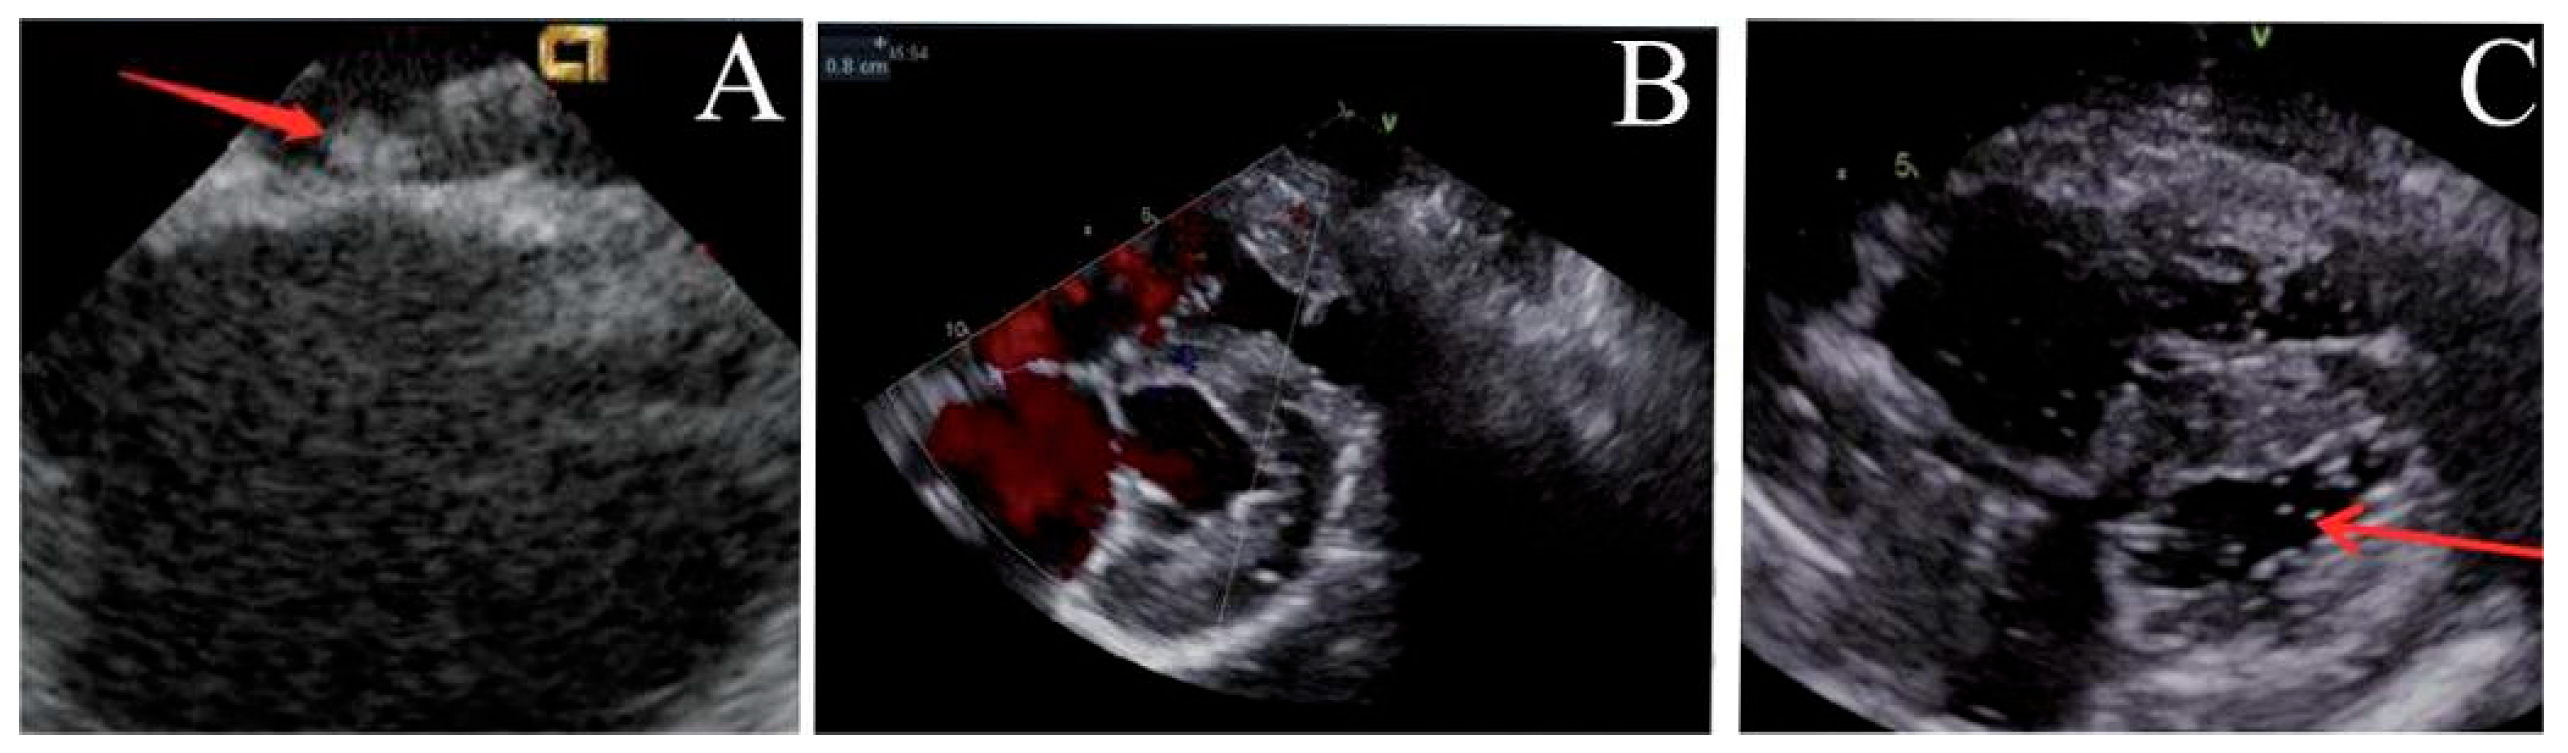

Post-implantation, the locking mechanism remained stable without suture breakage, thrombus formation, or neoplastic changes. The locking device was clearly visualized on ultrasound. Both the atrial septal defect diameter and residual shunt flow velocity decreased significantly over time, with near-complete defect closure observed by 6 months (postoperative ultrasound at immediate, 1, 3 and 6 months respectively, Fig. 3, Fig. 4, Fig. 5 and Fig. 6). Left ventricular hemodynamics and function remained unaffected.

Figure 5: Ultrasound observation three months after operation. (A) The locking node is intact, (B) the size of the atrial septal defect further decreases, and (C) there is no bubbles in the left atrium.

Figure 6: Ultrasound observation six months after operation. (A) The locking node is intact, (B) the size of the atrial septal defect further decreases, and (C) there is no bubbles in the left atrium.